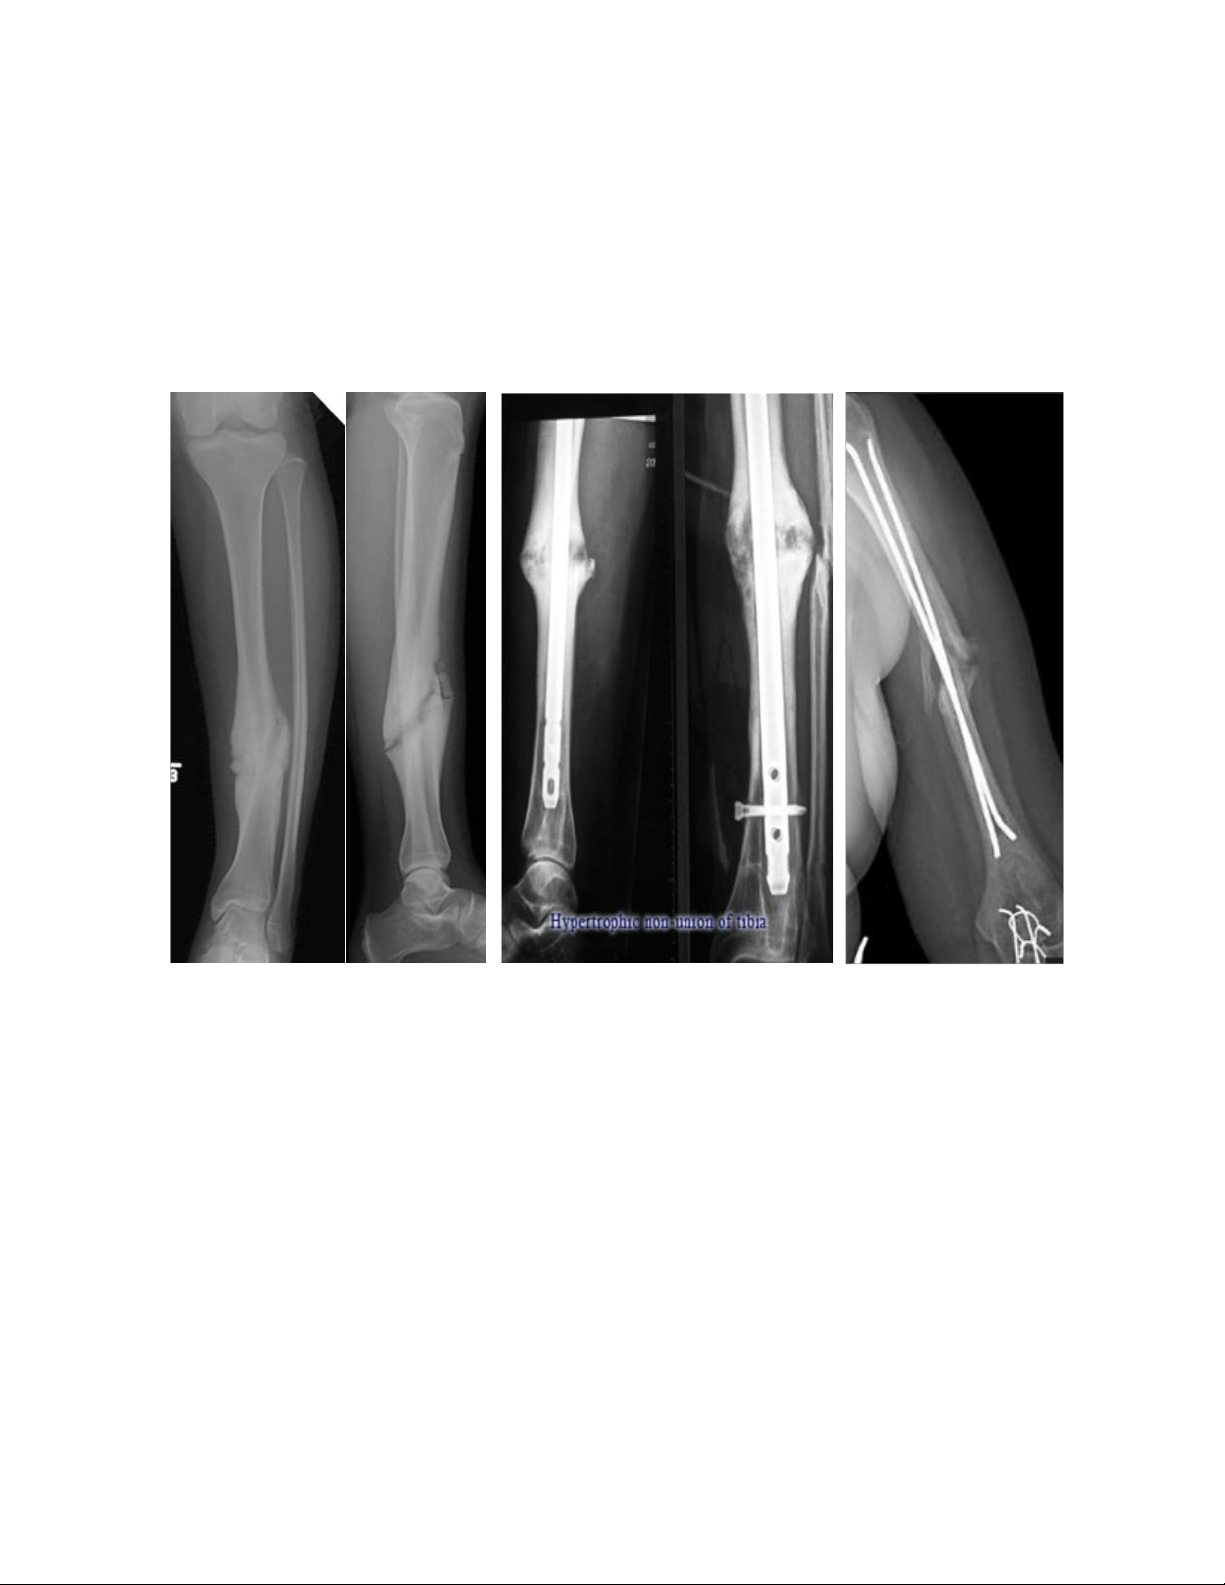

2.4.3. Chẩn đoán không lành xương

L â m s àng : ổ gãy còn cử động bất thường nhưng không đau khi vận động hay chịu lực.

X quang cho thấy còn khe gãy và ống tủy các đoạn bị bít kín ở các mặt gãy. lOMoAR cPSD| 39651089

Theo FDA (1986), không lành xương được định nghĩa là tình trạng xương

không liền sau tối thiểu 9 tháng và không có tiến triển gì trên X quang trong 3 tháng

liên tiếp. Vì các xương có thời gian lành rất khác nhau mà định nghĩa này chỉ đưa ra

một mốc thời gian chung là 9 tháng nên còn một số ý kiến không tán đồng. Tuy

nhiên cho đến nay, đây là định nghĩa duy nhất có đề cập đến mốc thời gian cụ thể

nên vẫn được sử dụng rộng rãi, đặc biệt là trong các nghiên cứu.

X Q u a n g k h ô n g là n h xư ơ n g 2.5.